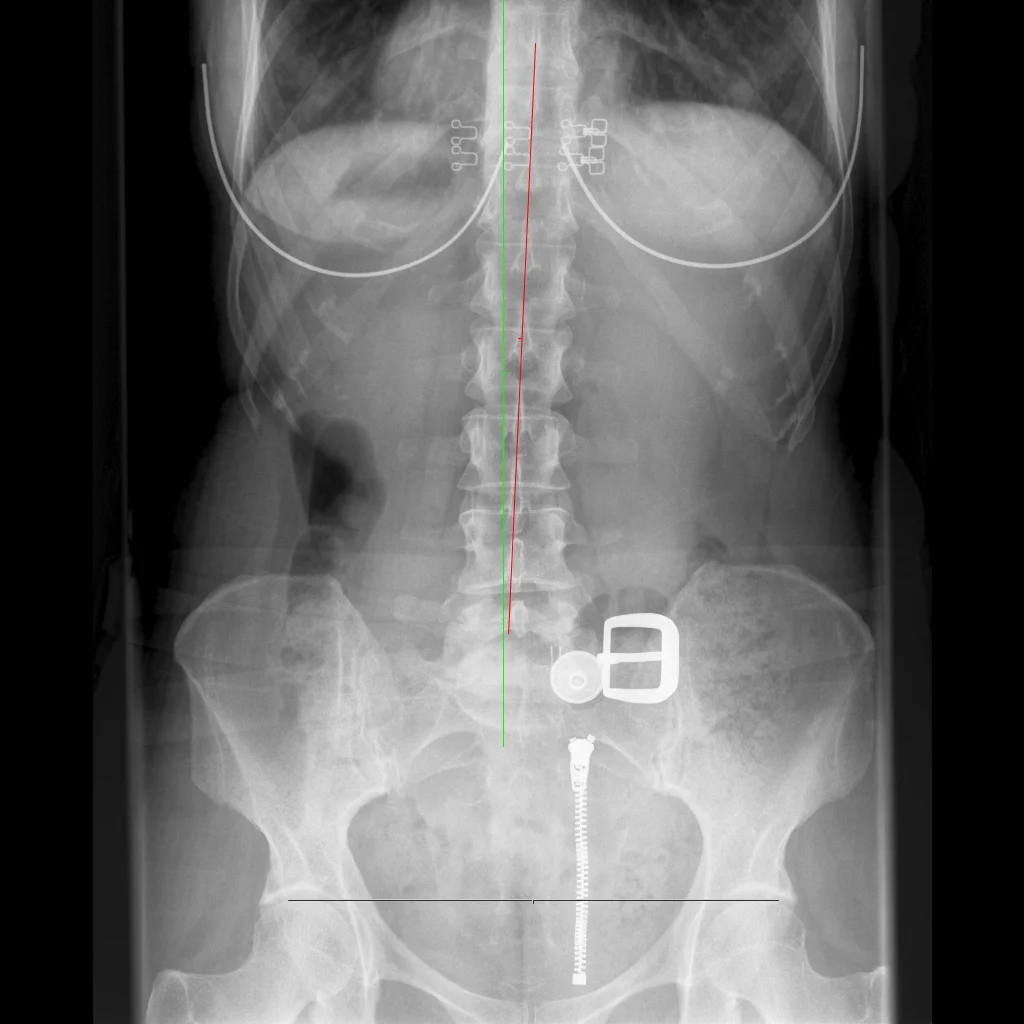

Posture Screen uses digital technology to capture your image and then assess any postural disturbances or imbalances.